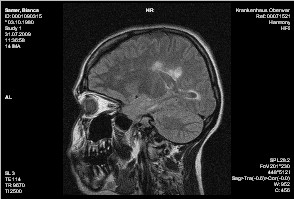

Cerebrum:

Es finden sich multiple, im Balken und periventriculär liegende rund-ovale und fingerförmige T2w hyperintense Glialäsionen, von ihrer Form vereinbar mit Enc. diss. Weiters Glialäsionen um die Hinterhörnder der Seitenventrikel und um das li. Temporalhorn. Die Läsionen zeignen kein Kontrastmittelenhancement.

Keine Ödemzonen. Normal weiter Liquorräume.